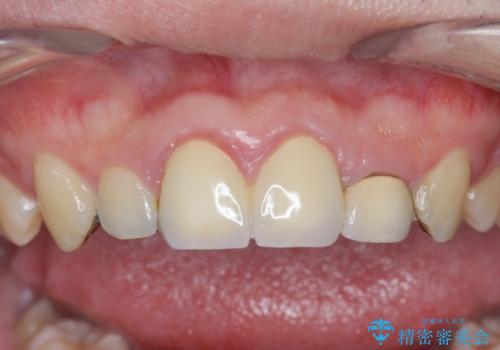

- 「前歯の見た目、歯ぐきの腫れを改善したい。」と希望され来院されました。

前歯には接着性の維持装置や、中途半端な形の連結クラウンが装着され、清掃性が悪く歯ぐきの腫れや、歯ぐきの形態の不揃いが認められました。

歯周外科を行ったことで、歯ぐきの形態や腫れが改善され、審美性だけでなく清掃性も大きく改善することができました。